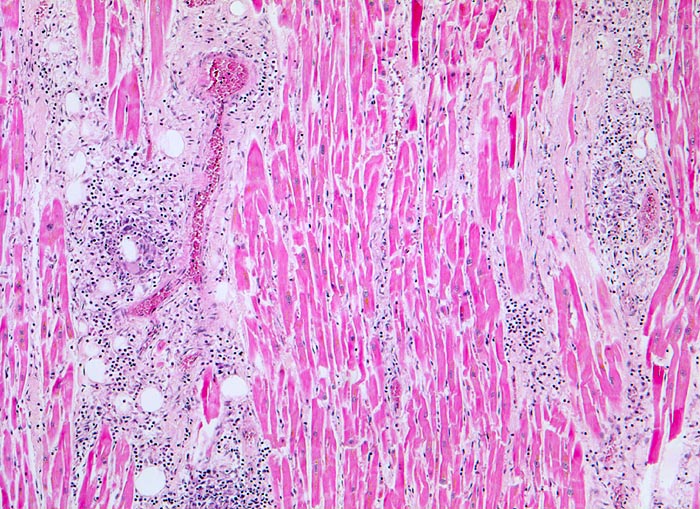

Im Intersitium, besonders perivaskulär und zwischen den Gefässbündeln zahlreiche Herde von gemischten Entzündungsinfiltraten.

Patientin plötzlich tot im Bett aufgefunden nach mehreren Osteosynthesen. Vorgängig Zeichen einer hyperergischen Reaktion mit Urticaria und Bluteosinophilie.